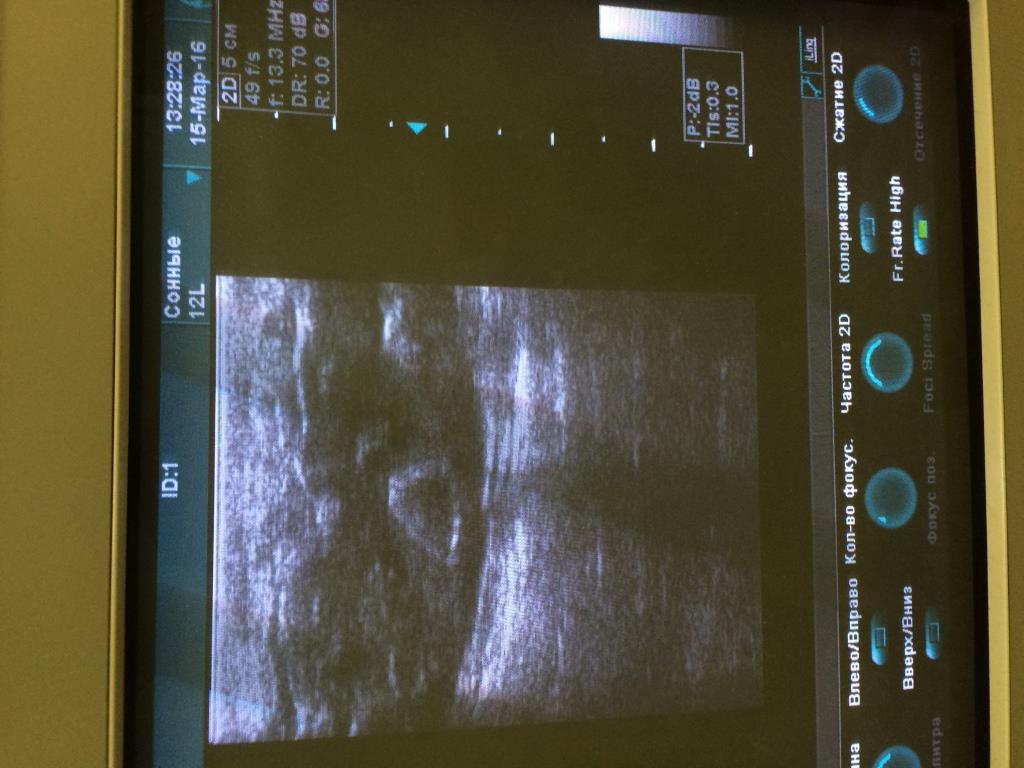

Аппарат Vivid 3 Pro корпорации General Electric Company (производственно-торговый бренд - "GE"), США, 2007 года.

При работе на конвексном и линейном датчике появляется картинка как на фото. Если убираю фокусные зоны либо понижаю частоту дефект пропадает.

Датчики вставлены в разные разъёмы. На конвексном есть небольшой порез акустической линзы, линейный без повреждений.

Предполагаю, что дело не в датчиках.